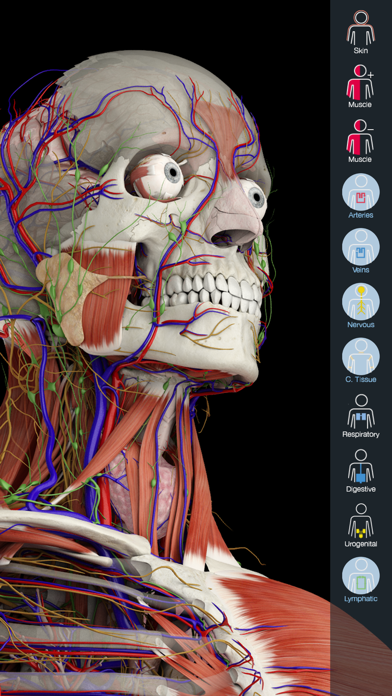

Downloading Essential Anatomy 5 IPA for iOS is a convenient and useful way to explore the world of human anatomy right from the comfort of your iPhone or iPad. This app provides a comprehensive and detailed view of the human body, allowing users to interact with various systems and structures. With stunning 3D graphics, it offers a visually captivating experience that aids in understanding and learning about the complexities of the human body. Whether you are a medical student, healthcare professional, or someone with a general interest in anatomy, Essential Anatomy 5 IPA is a must-have app that provides a wealth of knowledge at your fingertips. The app’s intuitive interface and easy navigation make it accessible to users of all levels of expertise. With just a few taps, you can delve into different layers of the body, explore various organs, muscles, and bones, and gain a deeper understanding of human anatomy. Download Essential Anatomy 5 IPA today and elevate your knowledge and appreciation of the human body.

The Essential Anatomy 5 IPA for iPhone is an incredible tool for medical students, professionals, and anyone interested in learning more about the human body. This app provides a comprehensive and detailed 3D model of the human anatomy, allowing users to explore and study different parts of the body with ease. With its user-friendly interface and interactive features, users can zoom in, rotate, and examine every angle of the human body, from bones and muscles to organs and systems. The app also provides in-depth information about each structure, making it a valuable resource for studying and understanding the intricacies of human anatomy. Whether you’re a medical student preparing for exams or simply curious about the wonders of the human body, the Essential Anatomy 5 IPA for iPhone is an essential tool to have at your fingertips.

Essential Anatomy 5 IPA MOD IOS is a revolutionary app that has changed the way we learn about the human body. With its advanced features and stunning visuals, this app provides an immersive and interactive experience for users. Whether you are a medical student, healthcare professional, or simply interested in learning about anatomy, Essential Anatomy 5 is a must-have tool. It offers a comprehensive library of detailed 3D models, allowing users to explore every aspect of the human body. From the skeletal system to the muscular system, nervous system to cardiovascular system, this app covers it all. Additionally, it provides in-depth information on each structure, including names, functions, and clinical relevance. With its user-friendly interface and intuitive controls, navigating through the app is a breeze. Overall, Essential Anatomy 5 IPA MOD IOS is an essential resource that brings anatomy to life, making it an invaluable tool for anyone interested in the human body.

This app provides a comprehensive and detailed 3D representation of the human body. With over 8,200 anatomical structures, including muscles, bones, organs, and more, it offers a level of accuracy and depth that is unparalleled. Whether you are studying for an exam or explaining a medical condition to a patient, Essential Anatomy 5 IPA has the information you need.

Essential Anatomy 5 IPA allows users to interact with the 3D models, zooming in and rotating them to explore every angle. The user-friendly interface makes navigating through the app a breeze, and the intuitive controls ensure that anyone, regardless of their level of expertise, can easily explore and understand the complex anatomical structures.

One of the standout features of Essential Anatomy 5 IPA is its ability to showcase cross-sectional views of the body. This enables users to see the internal structures and their relationships with each other, providing a deeper understanding of the body’s intricate systems. This feature is particularly useful for students learning about the different body cavities or professionals wanting to explain surgical procedures to their patients.